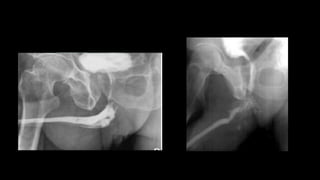

1. Patient supine with slightly tilted legs.

2. Using aseptic technique, the tip of the catheter is inserted so that the balloon lies

in the fossa navicularis and its balloon is inflated with 2–3mL

3. Contrast medium is injected and steep (30–45°) oblique films are taken.

• Gentle traction on the catheter is used to straighten the penis over the

ipsilateral leg and prevent urethral overlap